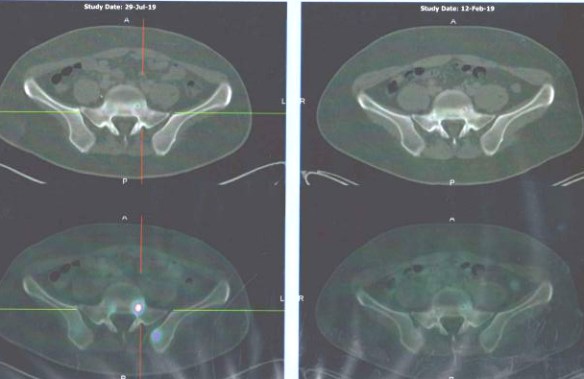

- PET scan on 14 September 2023 showed more serious condition.

- The metabolically active left lung mass with multiple neck, axillary and mediastinal nodes. Left pleura and bone lesions are likely due to primary lung malignancy.

- However, metastatic breast cancer recurrence cannot be excluded.